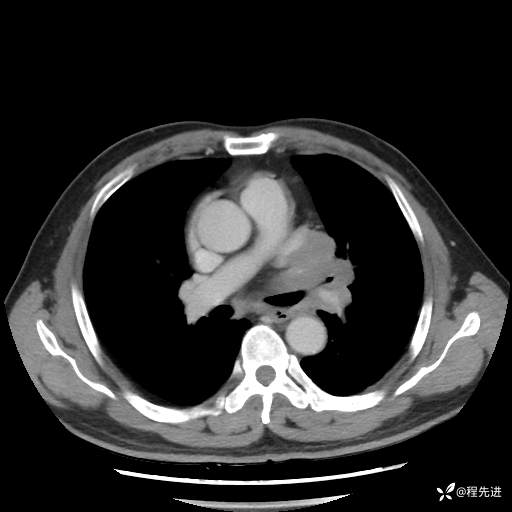

患者性别:男

患者年龄:57岁

简要病史:声嘶2月余

CT平扫+增强: